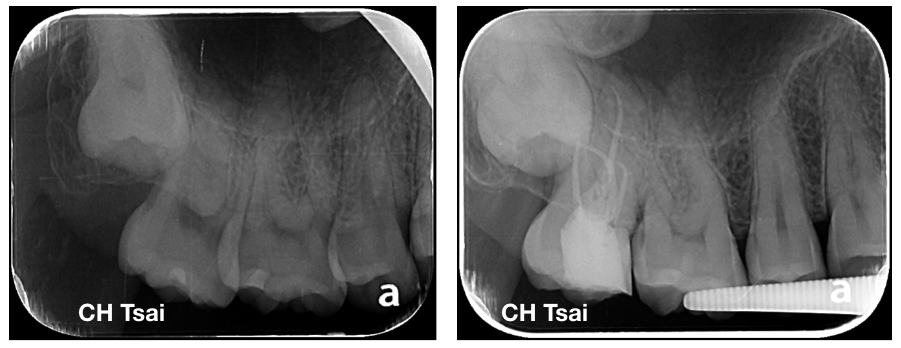

彎曲根管 發表於2023-06-032023-06-11 作者: 蔡承翰 in 未分類 右上顎第二大臼齒,牙髓炎伴隨自發性疼痛,經其他牙科醫師轉診治療; 全程在顯微鏡下完成根管治療療程。 完成治療後症狀緩解,建議病患繼續製作牙冠補綴物保護齒質。 右圖治療後可見近心牙根極度彎曲,且有額外(MB2)根管。 分享此文: 分享到 X(在新視窗中開啟) X 分享到 Facebook(在新視窗中開啟) Facebook 喜歡 正在載入... 相關 發表者:蔡承翰 中華民國牙髓病專科醫師 檢視 蔡承翰 的所有文章